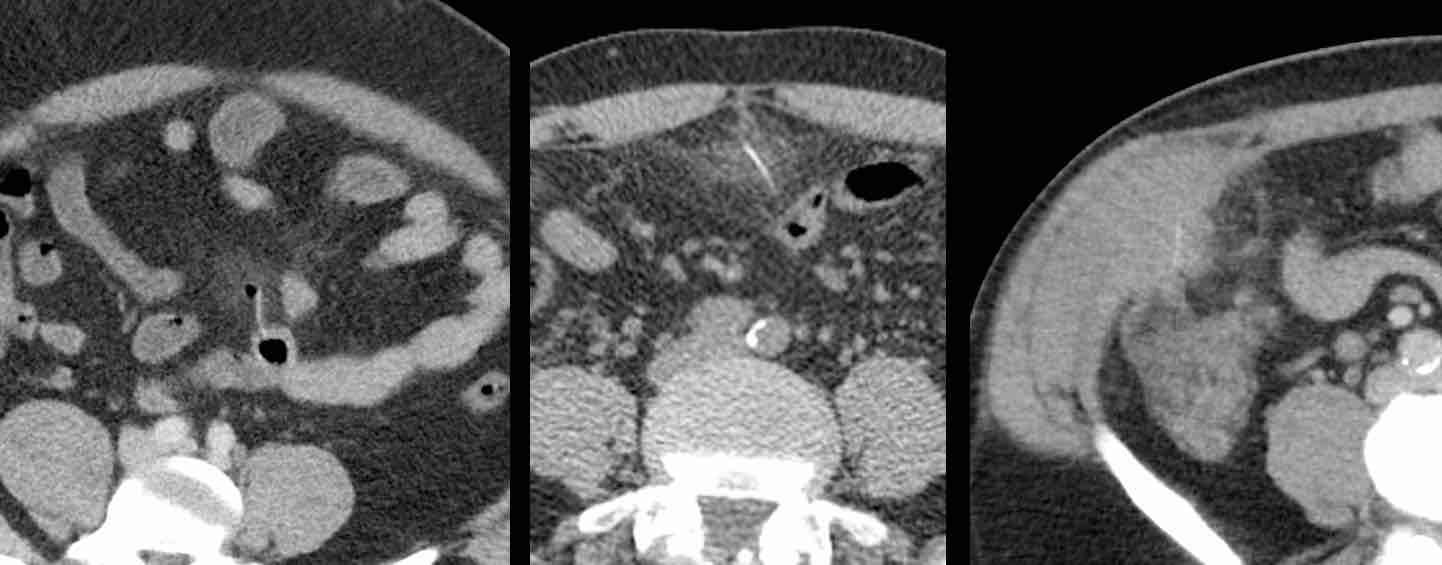

Bệnh nhân nam 53 tuổi nhập viện với khối đau hố chậu trái và CRP 173, nghi ngờ viêm túi thừa.

Bệnh nhân có tiền sử cắt thận trái 20 năm trước.

Siêu âm phát hiện áp xe thành bụng chứa một cấu trúc mỏng, đường cong (mũi tên).

CT không và có tiêm thuốc cản quang tĩnh mạch xác nhận xương cá (mũi tên) trong áp xe thành bụng có ranh giới không rõ ràng.

Lưu ý rằng xương cá có thể dễ dàng bị bỏ sót nếu chỉ chụp CT có tiêm thuốc cản quang tĩnh mạch.

Vị trí áp xe và xương cá được đánh dấu trên da.

Chỉ với một đường rạch rất nhỏ, mủ và xương cá đã được lấy ra. Hồi phục không biến chứng.